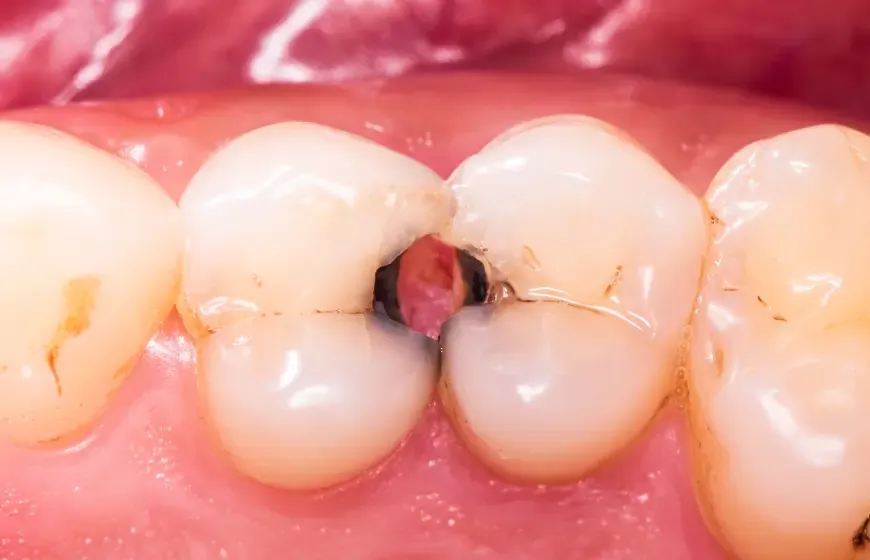

Kiedy już pacjent wygodnie usiądzie, zaczyna się właściwy przegląd. Moje oczy skanują każdy ząb, szukając nawet najmniejszych oznak problemów. Oczywiście, próchnica jest na pierwszym miejscu szukam ubytków, przebarwień, które mogą świadczyć o początkowej demineralizacji szkliwa. Ale to nie wszystko. Sprawdzam również, czy nie ma pęknięć szkliwa, które mogą być wynikiem urazów lub nadmiernego obciążenia zębów. Oceniam stopień starcia zębów, co często jest wskazówką do problemów ze zgryzem lub bruksizmu. Przyglądam się też istniejącym wypełnieniom i koronom, aby upewnić się, że są szczelne i prawidłowo funkcjonują.

Bruksizm, czyli nieświadome zgrzytanie lub zaciskanie zębów, to problem, który dotyka coraz więcej moich pacjentów, często związany z przewlekłym stresem. Niestety, wiele osób nie jest świadomych tego nawyku, zwłaszcza jeśli występuje on głównie w nocy. Ja jednak widzę jego skutki bardzo wyraźnie. Patologicznie starte powierzchnie zębów, często z charakterystycznymi płaskimi fasetami, są dla mnie jasnym sygnałem. Obserwuję również pęknięcia szkliwa, a nawet złamania koron zębów czy wypełnień. Pacjenci często skarżą się na bóle głowy, karku czy sztywność mięśni żuchwy. Moja rola polega wtedy na zdiagnozowaniu problemu i zaproponowaniu rozwiązań, takich jak szyny relaksacyjne, które chronią zęby przed dalszymi uszkodzeniami.